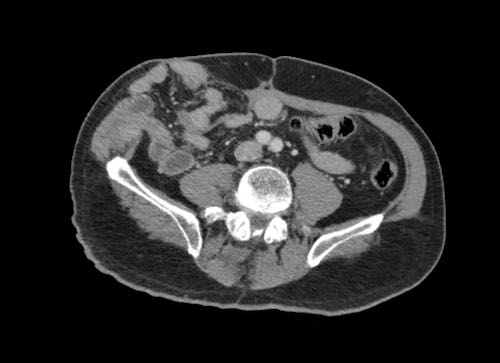

Hình ảnh

Hình ảnh CT của một bệnh nhân ung thư phúc mạc.

Một lượng nhỏ dịch cổ trướng hiện diện ở góc phần tư trước bên phải.

Các đường dày dạng nốt vuông góc với thành ruột được ghi nhận.

Hình ảnh này đại diện cho tổn thương xâm lấn mạc treo ruột lan rộng (mũi tên).